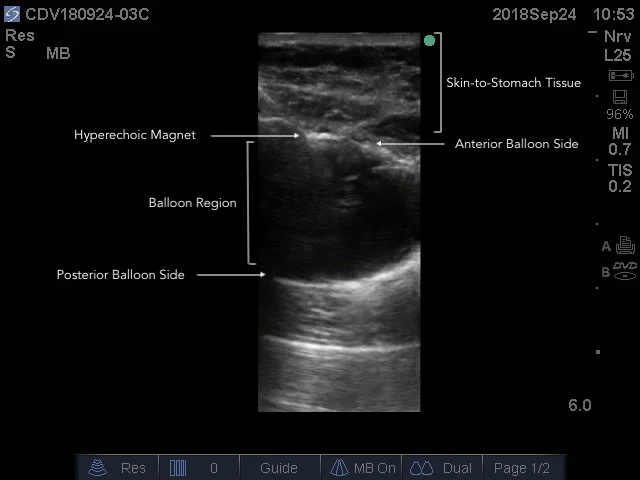

Annotated Ballon Visualization of Ultrasound Gastrostomy

February 15, 2019 Howard Carolan

Balloon Visualization_annotated.jpg